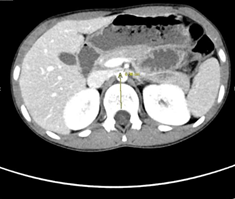

Fig 2 :Axial image of IV contrast enhanced CT scan of the abdomen demonstrates aortomesenteric narrowing (4 mm) (Normal range > 10 mm).

The tight and sharp aortomesenteric distance and angle respectively along with the gastric and duodenal dilatation are in favour of superior mesenteric artery syndrome.

Figure 2